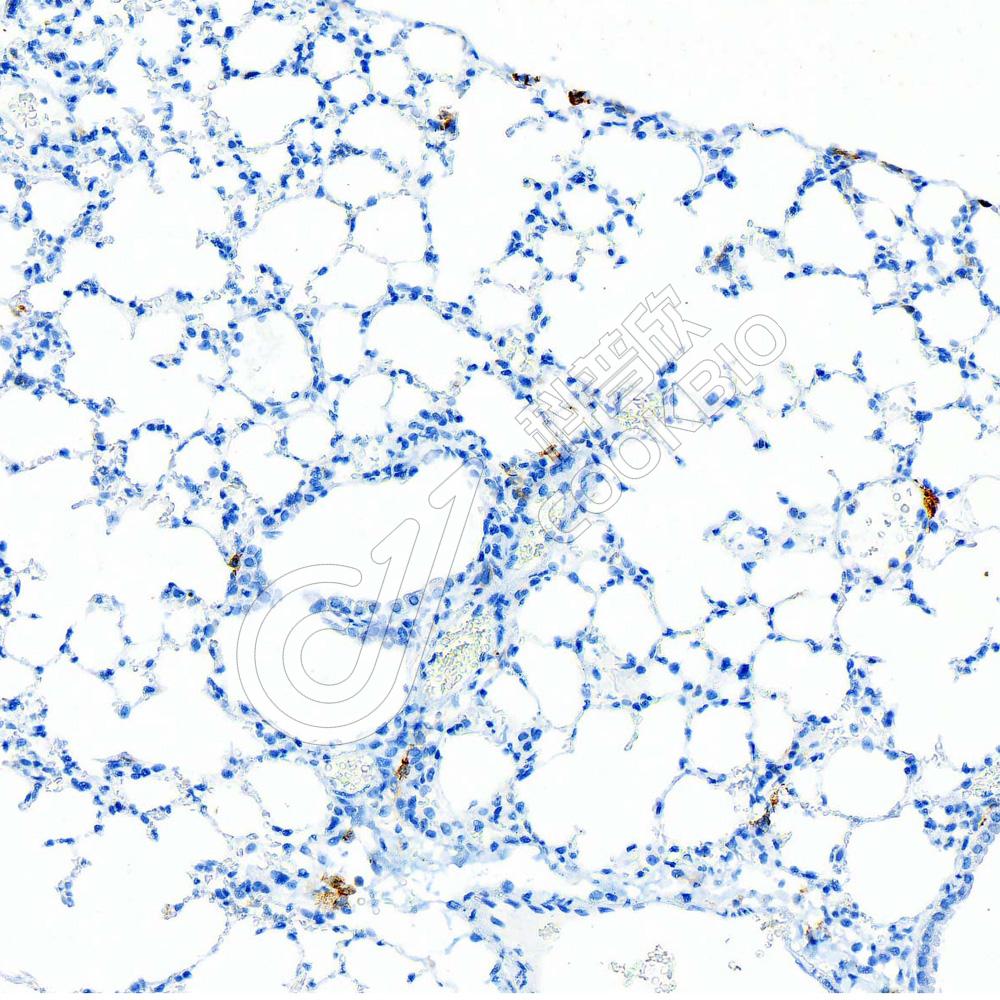

IHC检测CD86蛋白(货号 K5450162).

样品: 小鼠lps(24h)肺诱导炎症模型, 4%多聚甲醛 (货号KSG1101) 固定12-24小时.

抗原修复: 柠檬酸抗原修复液(干粉, pH 6.0) (KSG1201), 高压锅均匀喷气计时2分钟.

—抗: 1: 1000稀释, 4℃ 孵育过夜.

二抗: S-vision免疫组化多聚二抗(山羊抗兔),即用型 (货号KB3906), 室温孵育20分钟.